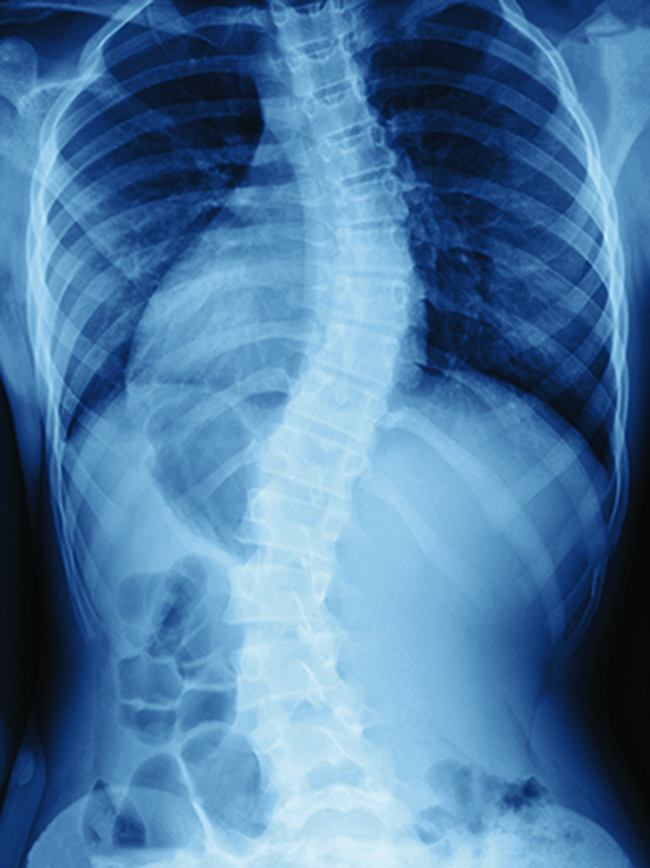

Scoliosis

Usually caused by unknown reasons around curved spine c-shaped or s-shaped, and some are spirally shape.